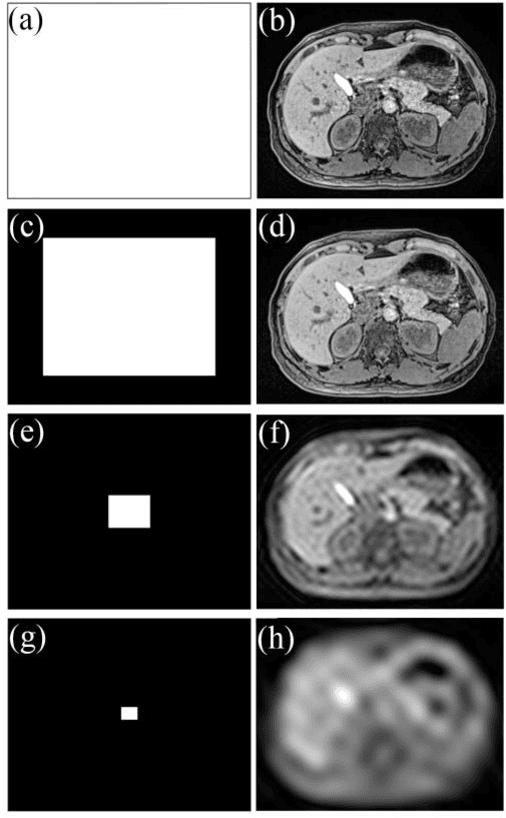

Abstract:Dynamic MRI is a technique of acquiring a series of images continuously to follow the physiological changes over time. However, such fast imaging results in low resolution images. In this work, abdominal deformation model computed from dynamic low resolution images have been applied to high resolution image, acquired previously, to generate dynamic high resolution MRI. Dynamic low resolution images were simulated into different breathing phases (inhale and exhale). Then, the image registration between breathing time points was performed using the B-spline SyN deformable model and using cross-correlation as a similarity metric. The deformation model between different breathing phases were estimated from highly undersampled data. This deformation model was then applied to the high resolution images to obtain high resolution images of different breathing phases. The results indicated that the deformation model could be computed from relatively very low resolution images.